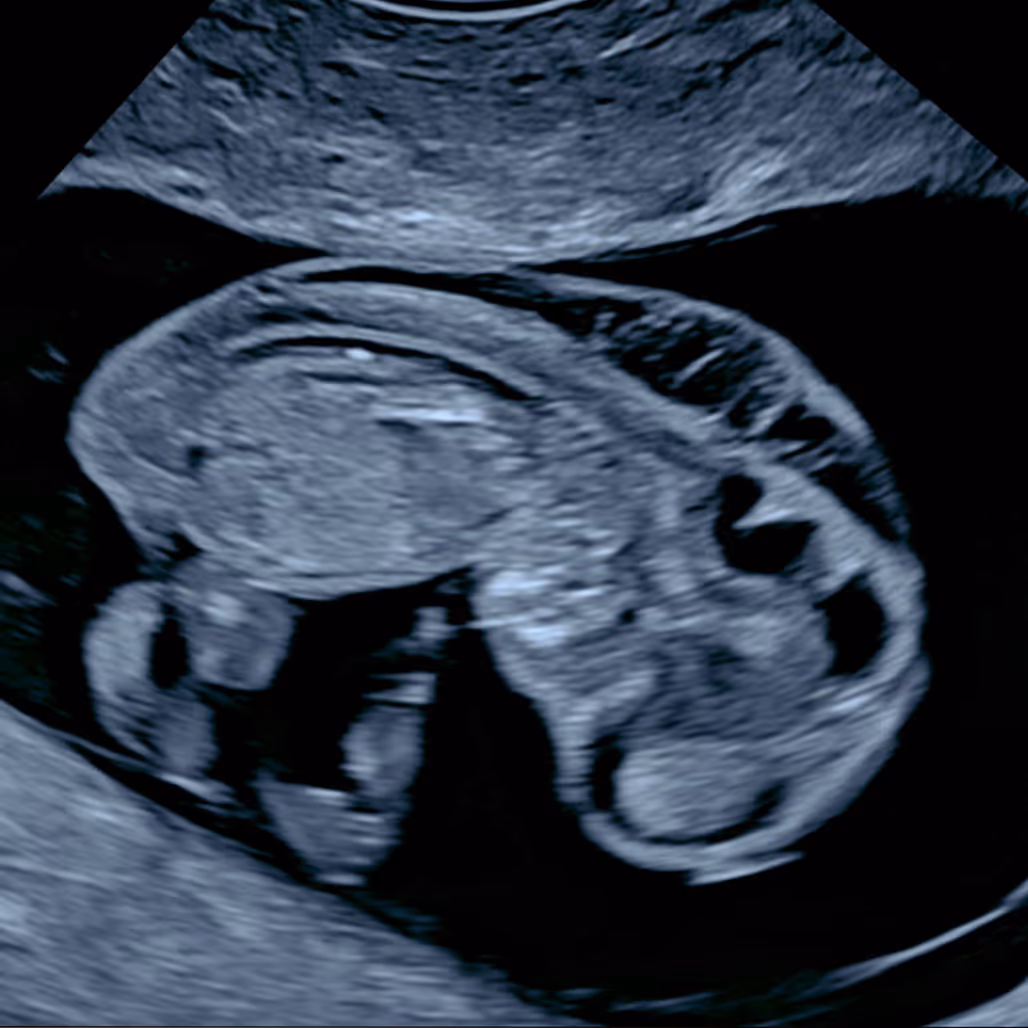

A cystic hygroma is a large fluid-filled swelling that develops at the back or sides of a baby’s neck due to abnormal development of the lymphatic system. On ultrasound, it often appears as a multiloculated (divided by thin walls or “septa”) fluid space - hence the term “septated cystic hygroma.” Fetuses with cystic hygromas usually have markedly increased NT measurements. This condition is often associated with chromosomal or genetic abnormalities, although in some cases it may occur in healthy pregnancies and resolve on its own.